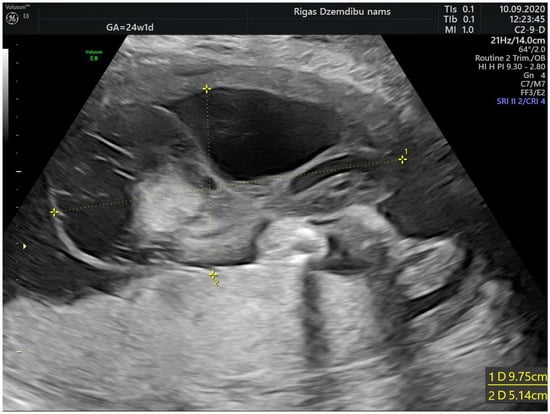

The size of the solid component was 3.4 × 2.3 cm and did not change during the pregnancy. The umbilical arteries and vein were running around and through, extra vessels were not observed in the tumor (Figure 2a). At the follow-up, the mass had rapidly enlarged in the size, from 285.32 cm3 at 26 weeks to 1929.36 cm3 at 32 weeks (Figure 2b). As well the reduction of fetal growth was observed from 30th week of gestation (Figure 3b).

Figure 2.

(a) Umbilical vessels going through the tumor at 32 + 2 weeks by 3D static HD flow (glass mode) imaging; (b) Tumor appearance at 32 + 2 weeks.

The latest development of high-resolution ultrasound machines and 3D technology yields diagnostic accuracy of umbilical cord anomalies such as true knots, cord aneurysms, cysts, hematomas, excessive/ absent coiling, true cord tumors etc. [11,12,13]. Volume acquisition of the vessels by static 3D in combination with color Doppler can be used to assess angioarchitecture and differentiate vascular malformations applying different displays, including glass-body mode, when blood flow can be visualized together with the surrounding structures [14]. In our case the tumor was detected by 2D mode and additional application of the high definition (HD) flow Doppler allowed to delineate the course of blood vessels, their coiling and blood flow within the tumor. High resolution images may provide auxiliary information to the real 2D ultrasound, therefore facilitate management, patient consultation and even prognostication.